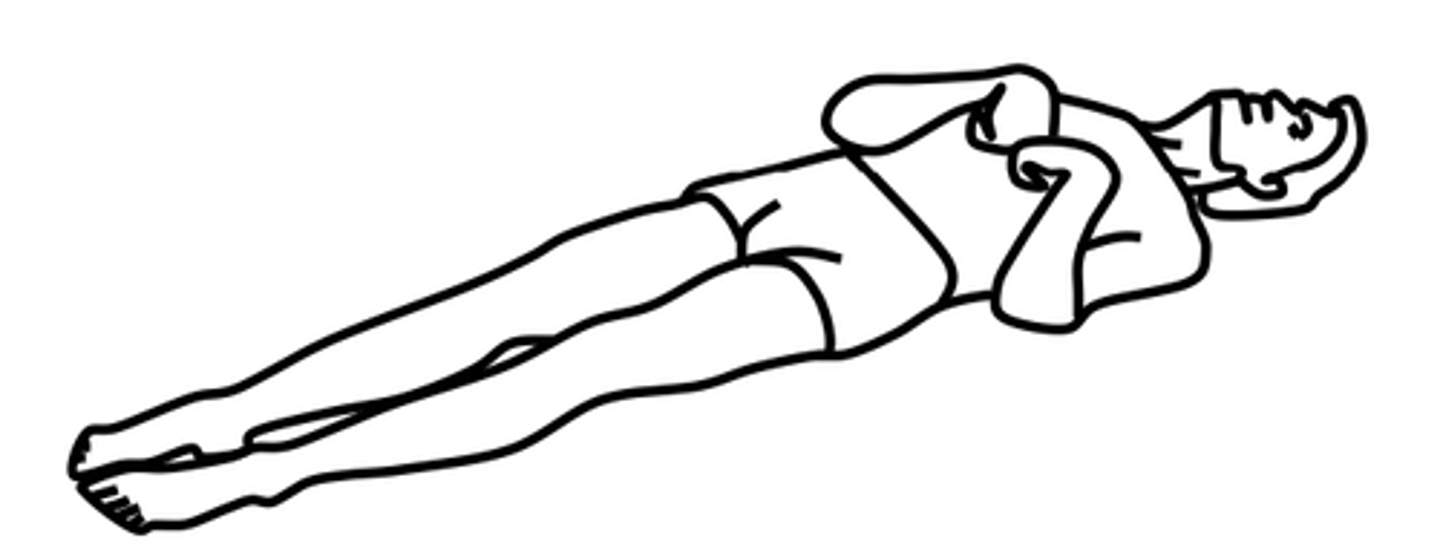

What is decorticate posturing?

Hands pulled to chest and hyper-extended. Internal rotation and adduction of the arms with flexion of the elbows, wrists & fingers.